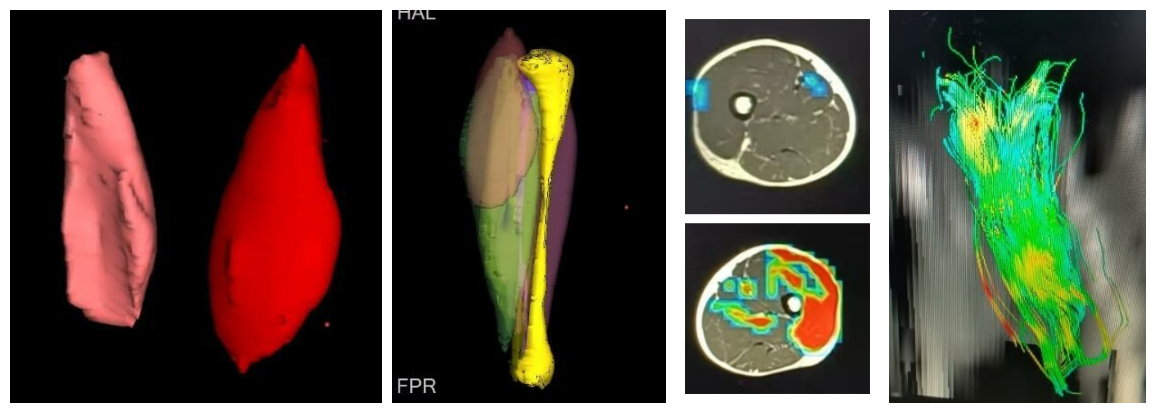

3月:多次和手外科合作探索肌肉磁共振成像重建技术,肌肉功能评估,肌纤维成像等(图5)。

图5肌肉磁共振成像重建技术,肌肉功能评估,肌纤维成像。